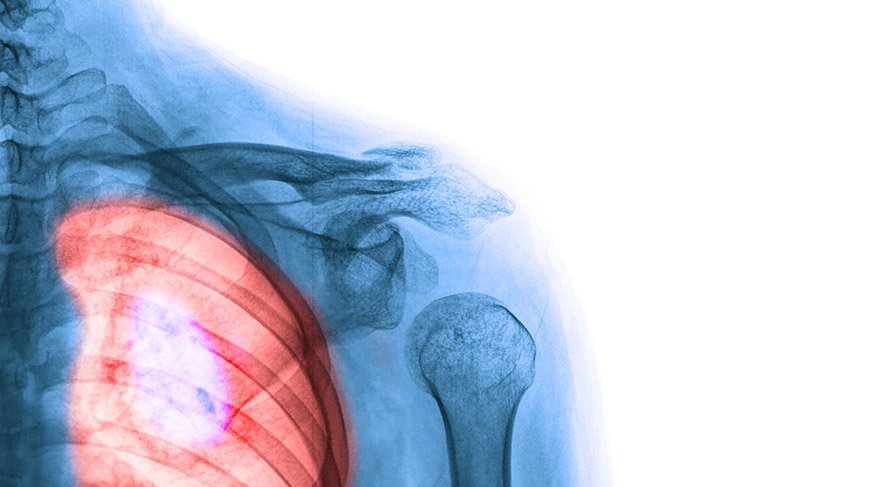

Yapılan çalışmalar akciğer kanserinin ülkemizde hem erkeklerde hem de kadınlarda damar hastalıklarından sonra ikinci ölüm nedeni olduğuna dikkat çekiyor. Başta sigara olmak üzere, genetik faktörler, yanlış beslenme, yaş faktörü ve bazı riskli meslek grupları akciğer kanserine davetiye çıkarıyor. Erken evrede cerrahi ile tedavisi mümkün olan akciğer kanseri sinsi ilerlediğinden ve genellikle ileri evrede belirti verdiğinden tanı aşamasında gecikmeler yaşanabiliyor. Bu da kanserin tedavi aşamasını sekteye uğratıyor. Ancak geliştirilen multidisipliner tedavi yaklaşımları uygun ileri evre akciğer kanseri hastalarına umut oluyor.

Akciğer kanserinin oluşumu ve yapısı ile ilgili bilgi veren Doç. Dr. Özkan Demirhan,” Yengecin avını kıskacı ile kavrayıp yavaş yavaş yemesinden ilham alınarak; kelime anlamı yengeç olan kanser genellikle karsinojenlerin sinyal iletim yollarını bozması ile gerçekleşen, organizmanın kontrolü dışındaki hücre çoğalmasıdır. DNA yapısının bozulması ile başlayan çok basamaklı, genotoksik bir olaydır. Bütün kanser türlerinde ölümler, organizmanın sinyallerine cevap vermeyen tümöral dokunun kendisinden çok geliştirdiği metabolik değişikliklerden kaynaklanmaktadır. Ülkemizde erkeklerde prostat kanserinden sonra en sık, kadınlarda ise 5'inci sırada görülen kanser tipidir.” dedi.